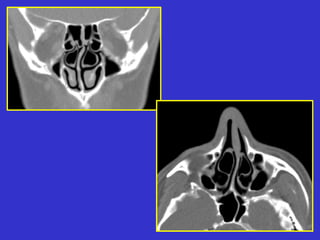

Este documento describe las diferentes proyecciones radiográficas utilizadas para examinar los senos paranasales, incluyendo las proyecciones básicas de Caldwell, Waters lateral y las proyecciones especiales como Hirtz y Waters mentonasal. También describe las diferentes estructuras anatómicas que componen el complejo ostiomeatal anterior y posterior de los senos paranasales.